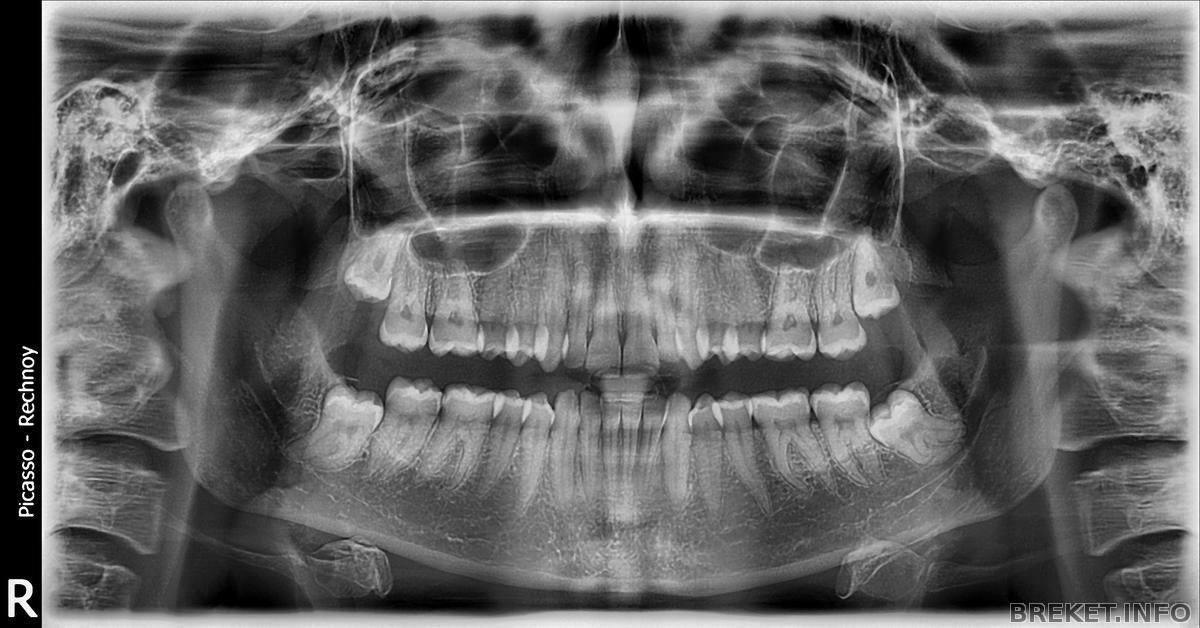

После расчета ТРГ и сделанного заключения, меня отправили на удаления одного зуба мудрости, который еще не вырос, но упирался в корень соседнего зуба.

На снимке его очень хорошо видно... К 25 годам у меня не вылез ни один зуб мудрости и мой орт сказала, что они и не вырастут... По этому отправила удалить только один зуб... Удаление было сложное, пожалуй, описывать весь процесс я здесь не буду ))) Хотя, возможно, рассказ получился бы интересным, но скажу одно, мучили меня 1 час 45 минут (По словам хирурга, его самое долгое удаление составило 40 минут, видимо мой случай он запомнит на долго

Почитав ваши дневнички я сделала вывод, что желательно удалять все зубы мудрости, и теперь меня тревожит тот факт, что я этого не сделала... Хочу спросить у вас совета, стоит ли мне удалять оставшиеся 3 зуба или же лучше положиться на мнения орта о том, что они у меня уже не вырастут и ничего не попортят?

Думаю, надо удалить, судя по снимку. Но тут, конечно, последнее слово за врачом